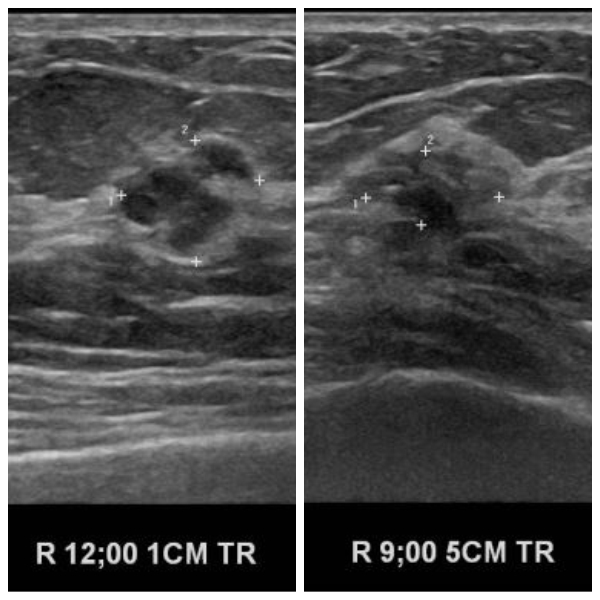

상기환자 건강건진상 이상소견으로 내원하신 60대 여성분으로 본원 초음파상 우측

12시 방향 1cm 의심스러운 멍울과 우측 9시 방향 5cm 의심스러운 멍울 조직검사 시행하여  우측 침윤성 유관암 진단 되었습니다.